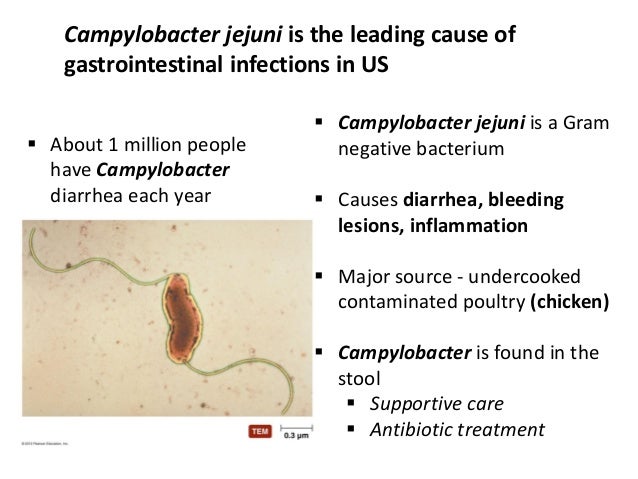

Кампилобактер фетус: патогенез и инфекции